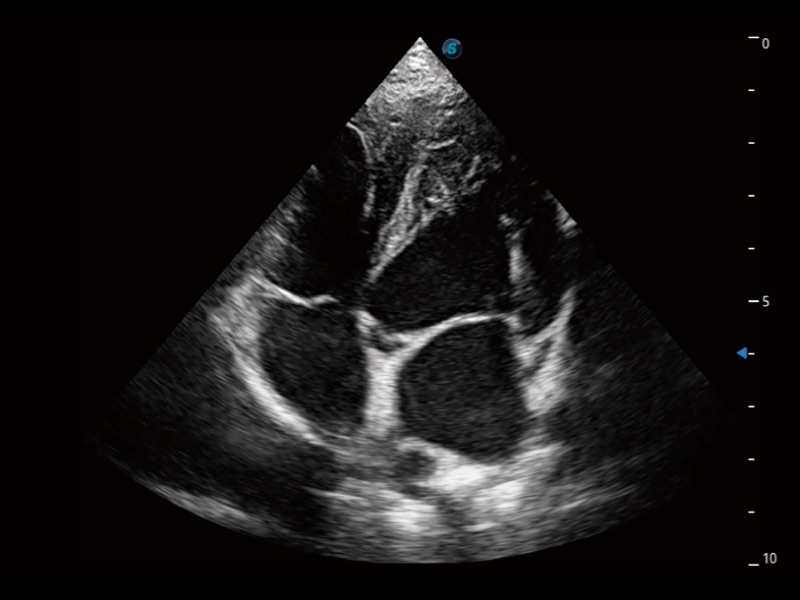

ProPet 70专为动物医生设计,对不同的动物体型和生理结构作出了针对性的优化。通过动物影像专用软件,可满足个性化的应用需求,帮助动物医生获得更精确的诊断数据。

为精细结构及组织边缘提供高清晰度的图像和更大的成像视野。帮助减轻医生的用眼疲劳,快速精准获得测量的数据。